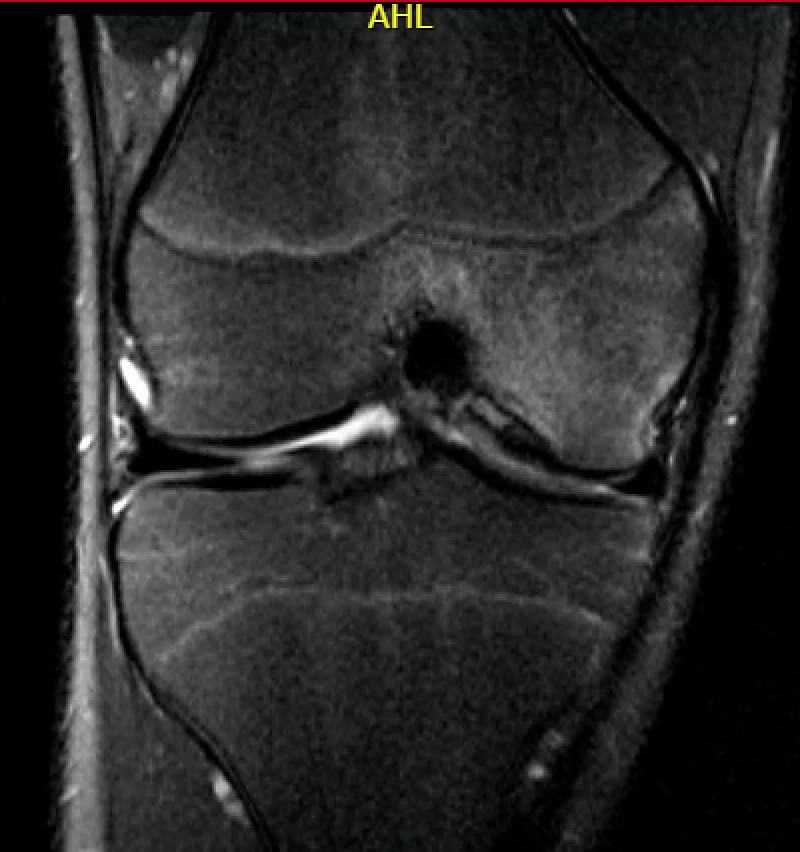

MFC OCD on presentation T2 image 6 months later

Stable lesion with no cysts Stable lesion with cysts